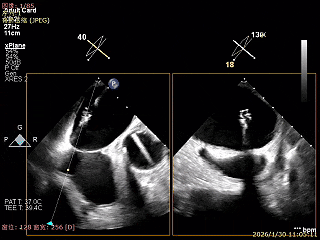

在1区进行轨迹测试和Orientation调整

将调整好的夹子移动至3区下左室

在左室打开夹子确认Orientation

捕捞瓣叶,确定瓣叶瓣尖稳定插入夹臂后,Gripper Down

Gripper Down后Bouncing明显

夹子关紧后,前后叶受限明显

夹子内侧反流消失

夹子外侧残余脱垂与反流

3D Enface下组织桥稳定残余外侧前叶脱垂

3D Enface上彩可见夹子内侧无反流,残余外侧反流